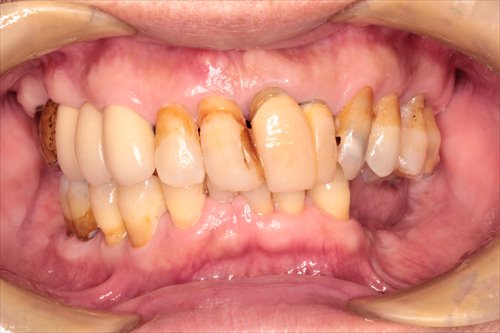

60代男性 歯周病で歯がぐらつく、無くなった場所があるとのことです。

残せない歯もあり、また、治療しなければならない歯も多々ありました。

ほとんどの歯を保険診療で治療した後、自費のミラクルデンチャーを装着しました。